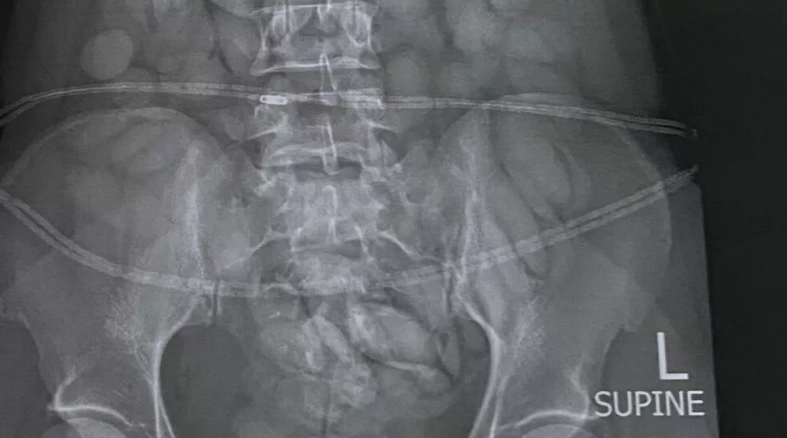

Sonxeber.az xəbər verir ki, bu barədə "The Mirror" nəşri məlumat verib. Bildirilir ki, hava limanında yoxlama zamanı qadının mədəsində narkotik vasitələr aşkarlanıb. Qadın saxlanılaraq xəstəxana aparılıb. Rentgen görüntüləri ilə qadının mədəsində yad cisimlərin olduğu təsdiq edilib.

Qadının mədəsində 60-a yaxən narkotik maddə aşkar edilib. Hazırda qadının mədəsində narkotik vasitələrinin çıxarılması istiqamətində işlər aparılır. Mütəxəssislər bildirir ki, qadının narkotik vasitələri torbaya qoyaraq udub. Qeyd edilib ki, qadının mədəsinin təmizlənməsi xeyli vaxt aparacaq: